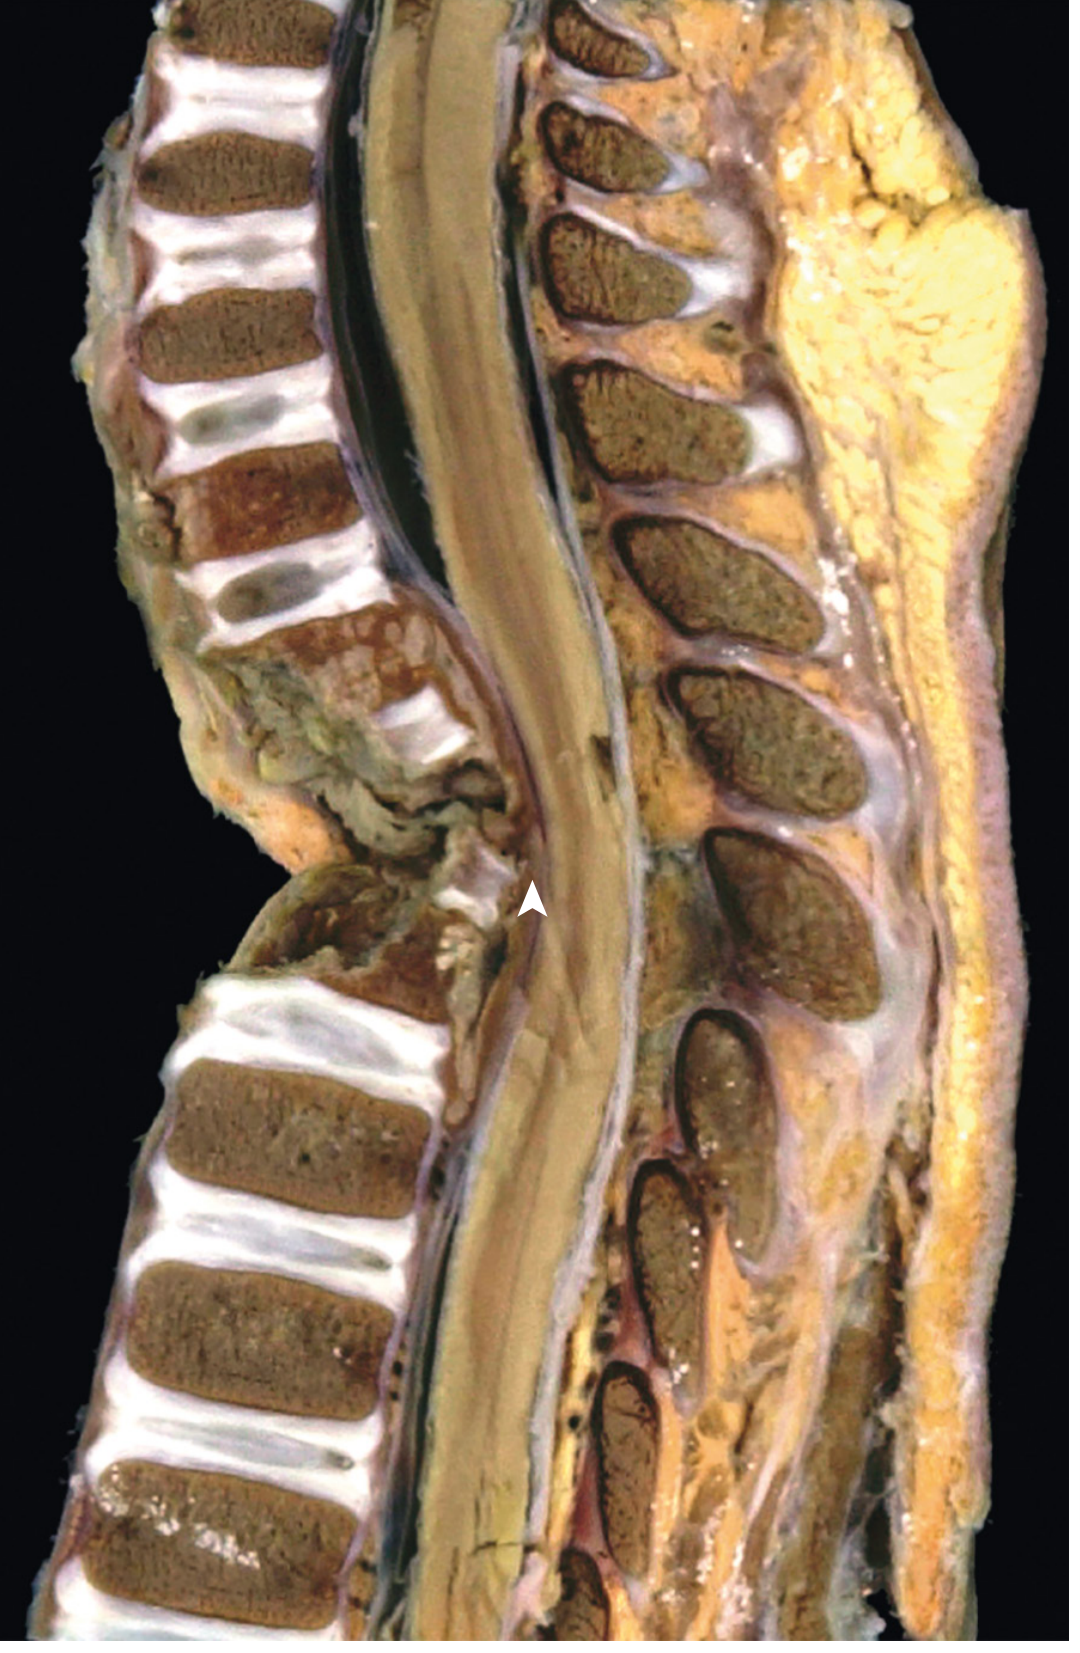

Pathology (Robbins)

• Infection destroys vertebral bodies and intervertebral discs

• Leads to compression fractures and kyphosis

• Granulomatous inflammation with caseous necrosis (mycobacterial osteomyelitis)

Pott disease - mycobacterial osteomyelitis of the spine showing vertebral destruction and kyphosis

Mycobacterial osteomyelitis of the spine (Pott disease) — infection has destroyed vertebral bodies and intervertebral discs (arrowhead), leading to compression fractures and kyphosis (Robbins Pathologic Basis of Disease)